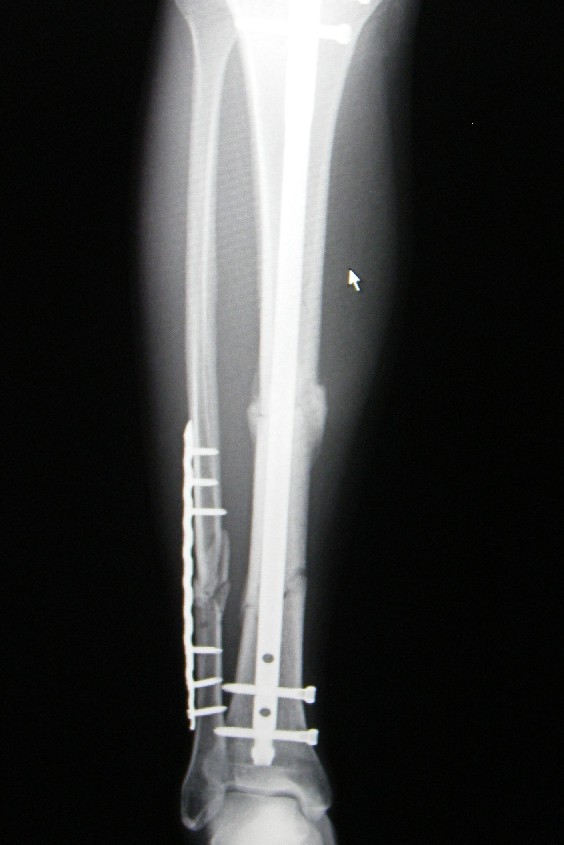

49637d85.JPG42b47a7f.JPGKAzの足の骨はこんな感じ。このお店から言うと、この骨は売り物になりませんね。それにしても骨って大事なものなんですね。こうして、痛みを伴うたびに、自分の足で歩けている事の大切さが身にしみます。これにておしまい!